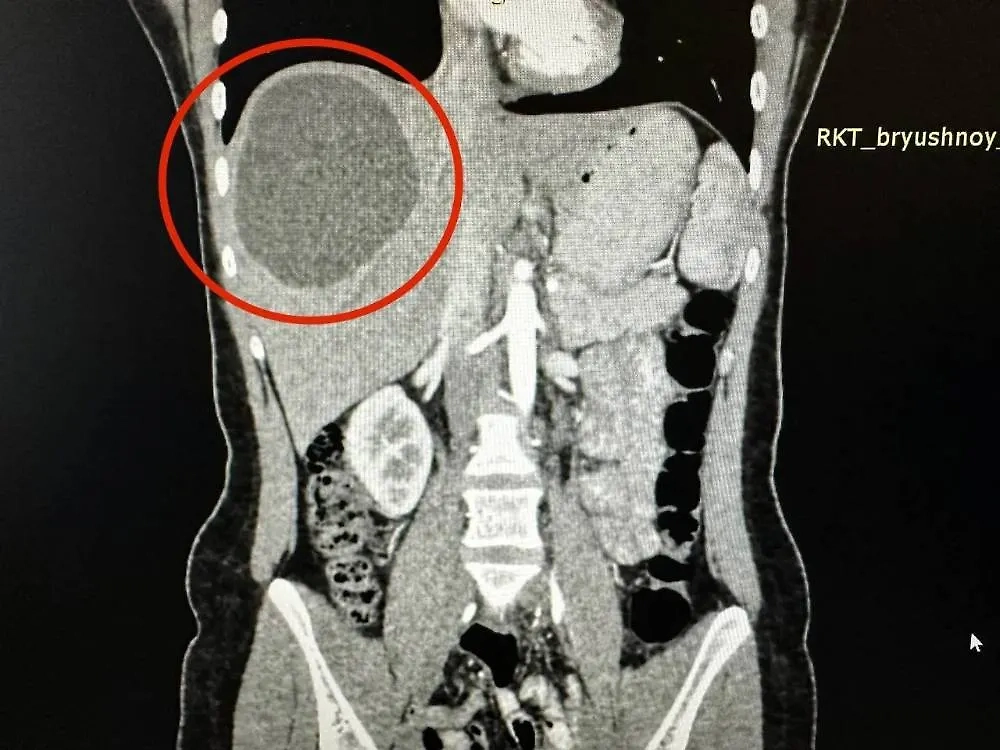

Киста в печени жительницы Казани. Обложка © VK / РКБ Татарстана

По информации сотрудников больницы, девушка обратилась за помощью из-за сильных болей в животе. Специалисты обследовали пациентку, обнаружив в её печени ком червей-паразитов, образовавших кисту 20 на 15 см.